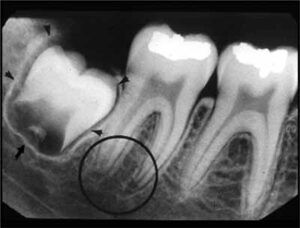

歯科X線写真における正常な解剖学_図4